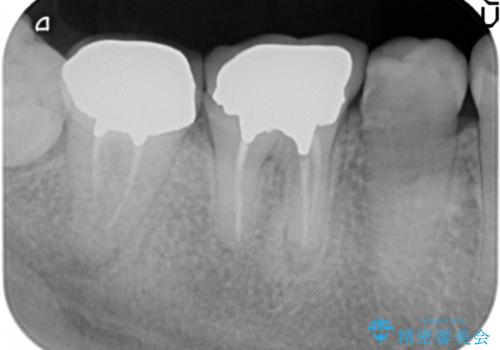

- 治療途中で放置してしまった奥歯の治療の続きを希望され来院されました。

奥歯は既に根管治療が為されクラウンを装着する必要性がある状態ですが、歯の高さが低くクラウンの安定性・強度を担保するために歯周外科を行う治療計画としました。